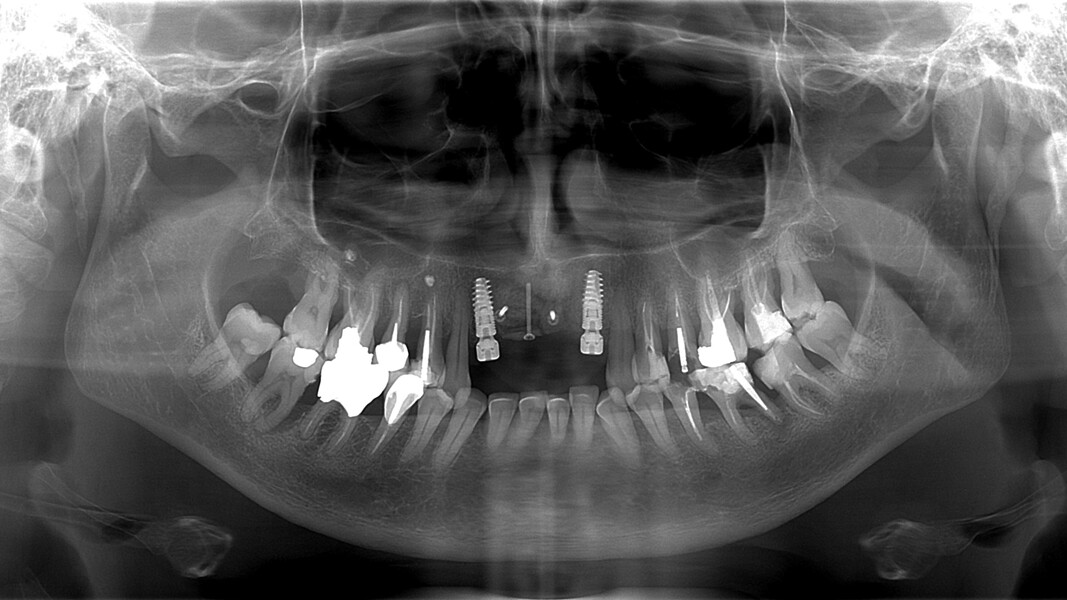

Une patiente de 49 ans nous a été adressée par l’un de nos confrères pour le remplacement de ses quatre incisives maxillaires (Fig. 23). Dans un contexte parodontal avancé, ses incisives centrales présentent une mobilité terminale (classe IV) elle n’ose plus les brosser de peur de les perdre lors de la manoeuvre. La patiente ne présente pas de problèmes de santé particuliers.

À l’examen, on observe une mobilité des quatre incisives maxillaires, une insuffisance osseuse verticale et horizontale, associées notamment au niveau de 11 et 21, la présence de plaque, de tartre et d’inflammation gingivale, surtout au niveau du bloc antérieur maxillaire. On note également la présence d’une dent de sagesse (dent 18) perdue (Figs. 24–26).

Le but du traitement est le remplacement des quatre incisives par un bridge implanto-porté de 12 à 22. Le plan de traitement mis en place est le suivant : extraction des deux incisives centrales et réalisation d’un bridge provisoire dento-porté fixe de 12 à 22 ; trois mois de temporisation permettant la cicatrisation des tissus mous, ainsi que la mise en oeuvre de la thérapeutique parodontale (Fig. 27) ; extraction de 12, 22 et 18, mise en place des implants, reconstruction de la crête (avec les racines extraites), mise en place d’un bridge provisoire fixe de 12 à 22, transvissé sur les deux implants.

Nous réalisons un lambeau avec une incision crestale décalée en palatin en 11 et 21, sulculaire en 12, 13, 22, 23, en prenant soin de préserver les papilles interdentaires, ainsi que deux décharges verticales en distal des canines. Nous réalisons un décollement de pleine épaisseur (Figs. 28 et 29). Les dents (12, 22 et 18) sont facilement extraites et les alvéoles curetées avec soins. Deux implants (4*13) sont positionnés dans la paroi palatine des alvéoles, il subsiste une déhiscence vestibulaire en 22. Les racines de 12, 22 et 18 sont séparées dans le sens de la longueur. Les racines préparées comme indiqué ci-dessus, sont vissées en vestibulaire et en occlusal de la crête, au moyen de vis d’ostéosynthèse (diamètre 0,9 mm), afin de reconstruire la crête osseuse au niveau des inters de bridge ainsi que la paroi vestibulaire de la crête au niveau de 22 (Figs. 30 et 31). Le gap vestibulaire entre les implants et la crête ainsi que l’espace entre la crête et le greffon au niveau de 21, sont comblés avec un matériau d’origine synthétique (Collapat II Symatese). Le lambeau est tracté, suturé coronairement avec un fil tressé synthétique 5.0 (Fig. 32). Des piliers coniques droits pour prothèse plurale transvissée sont posés, et une empreinte prise à la fin de l’intervention (Fig. 33). Un provisoire est réalisé dans la journée par notre laboratoire de prothèse et posé le soir même. (Figs. 34 et 35)

Les sutures sont retirées à 15 jours. Un contrôle de la bonne ostéointégration des implants est réalisé à 2 mois postopératoire (Figs. 36 et 37). La réalisation de la prothèse d’usage par notre correspondant intervient à 9 mois postopératoire (Fig. 38).

La patiente est suivie annuellement (cliniquement et radiologiquement), afin de contrôler l’évolution de l’ankylose des greffons radiculaires, leur résorption ainsi que le bon maintien du volume greffé (recul 48 mois postopératoire [Fig. 39]).